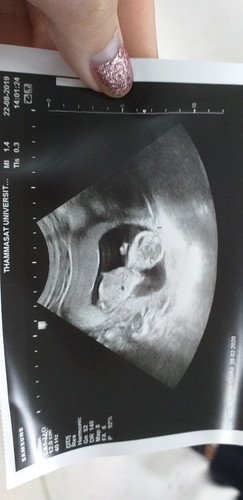

ตอนนี้เรากำลังตั้งท้องได้เกือบ 4 เดือนแล้วค่ะ ปกติแม่เป็นคนตัวเล็ก ผอม สูง มีแต่คนทักว่า หุ่นเหมือนไม่ได้ท้องเลย ท้องเล็กมากเลยค่ะ นูนๆนิดเดียวเอง แต่คุณหมอบอกน้องปกติดีนะคะ แม่กินเยอะด้วยค่ะ จะมีผลกระทบอะไรกับลูกมั้ยคะ / ท้องเล็ก ไม่แพ้ท้อง นอนทั้งวัน คนมีแก่บอกว่าจะได้ลูกชายจริงมั้ยคะ ?

เราได้14wแล้ว หุ่นก็เหมือนที่แม่พูดเลยนู้นขึ้นนิดเดียว น้ำหนักขึ้นมาแค่3ขีด (ฟังไม่ผิดค่ะ 3ขีด) เราไม่แพ้ท้องอะไรเลยกินได้ปกติ แต่ยังไม่ซาวลูก น่าจะวันที่1นี้แหละจะซาว บอกใครก็ไม่มีคนเชื่อว่าท้อง